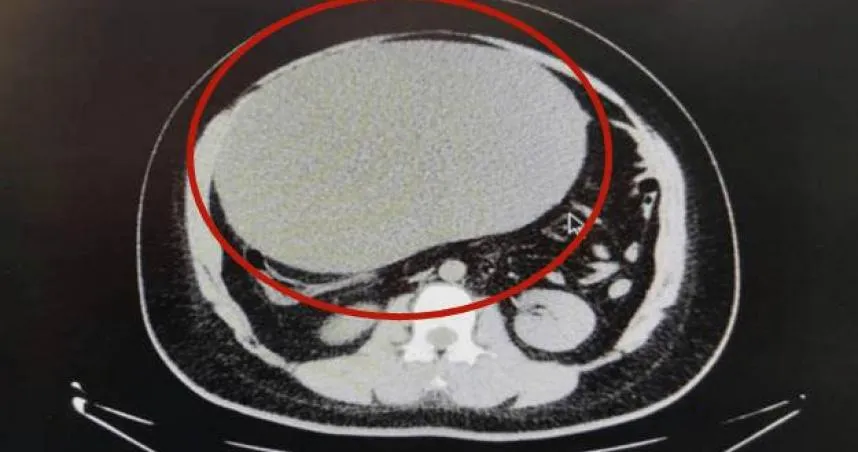

卵巢囊腫